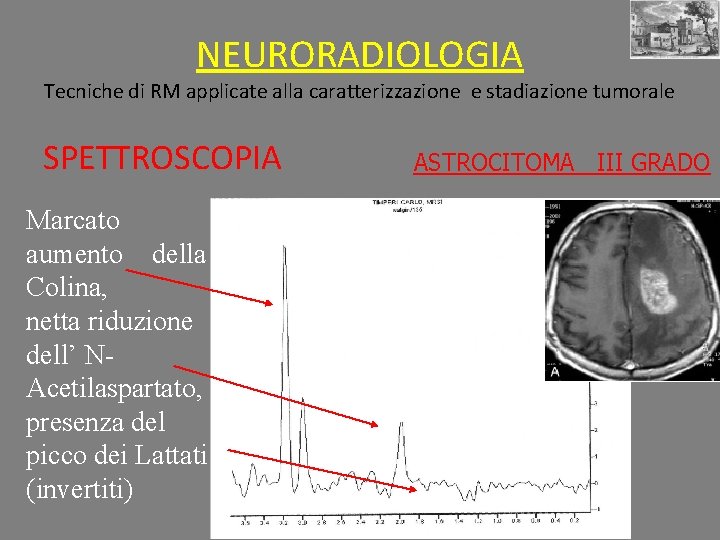

NEURORADIOLOGIA Tecniche di RM applicate alla caratterizzazione e stadiazione tumorale SPETTROSCOPIA Marcato aumento della Colina, netta riduzione dell’ NAcetilaspartato, presenza del picco dei Lattati (invertiti) ASTROCITOMA III GRADO